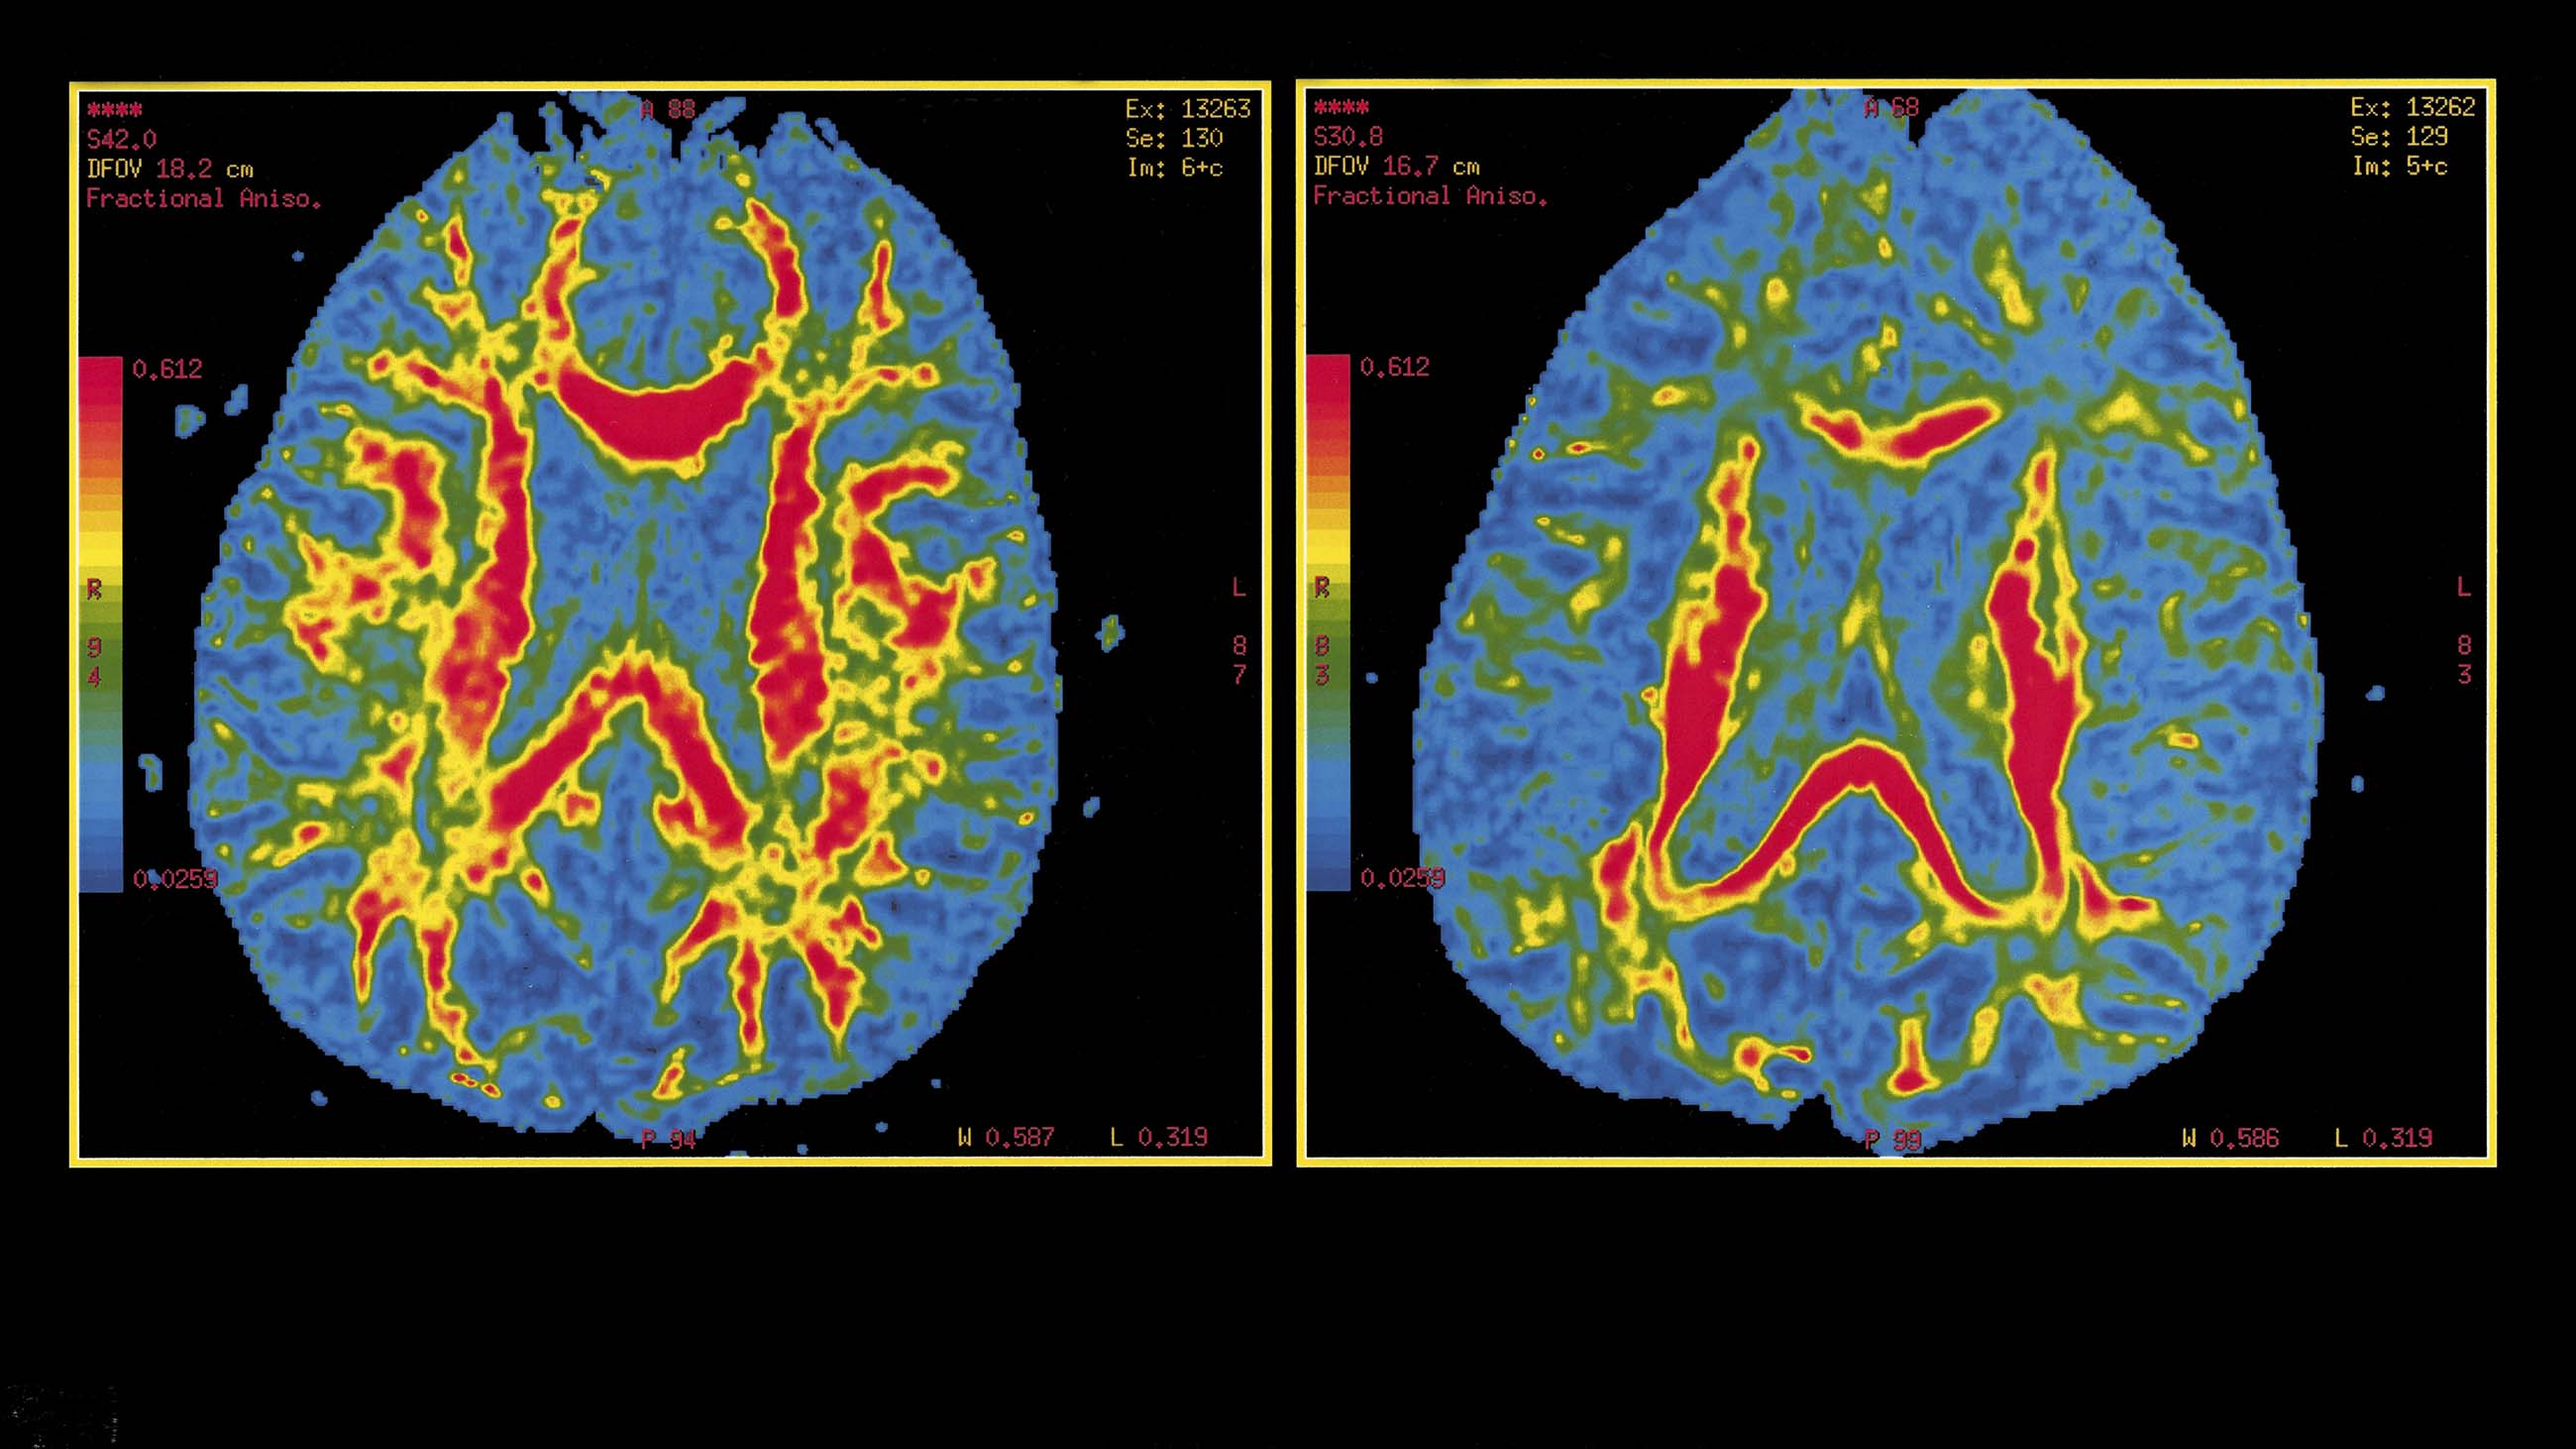

وبنهاية مدة الدراسة، التي تم نشرها بمجلة داء الزهايمر العلمية المتخصصة Journal of Alzheimer's Disease، وجد الباحثون تحسناً في الأداء الذهني والاتصال بين خلايا المخ لدى سبعة من أصل ثمانية من المشاركين في التجربة، حيث أثبتت التحاليل تراجع بروتينَي تاو واميلويد-بيتا المرتبطين بالإصابة بالخرف.

كما أثبت مسح المخ، الذي تم إجراؤه لجميع المشاركين في التجربة، بهدف الكشف عن أي أعراض جانبية، عدم نمو أورام أو حدوث نزيف داخلي بسبب العلاج الجديد.